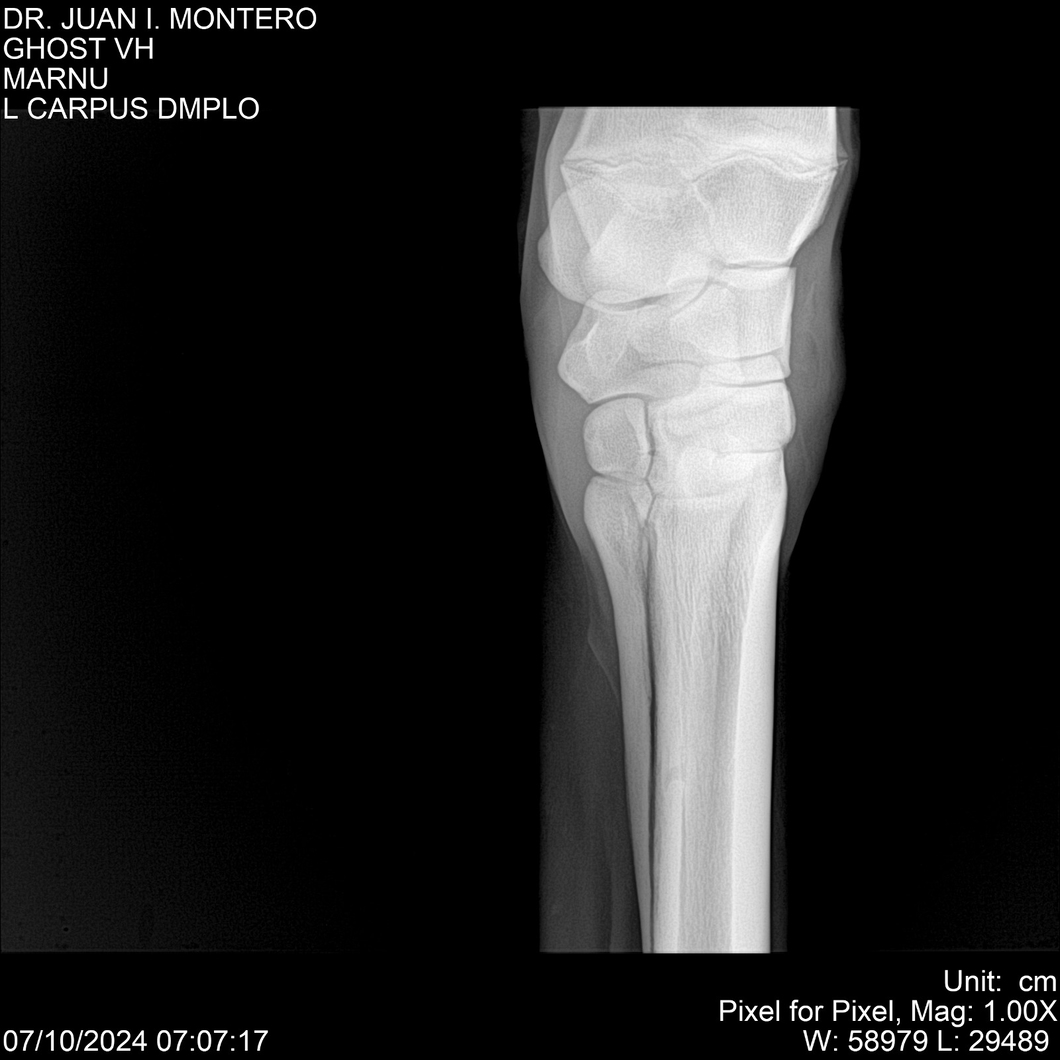

LOTE 15, GHOST VH 🔥 🔥 🔥 Lote Anterior Volver al remate Lote Siguiente Ficha Contacto Montevideo - Ficha del Lote Identificador: #282525 Categoría: Yeguarizos Montevideo - 69 Visualizaciones ClicData Contacto Empresa: Abelenda N. R., Walter Hugo Nombre*: Teléfono* : E-mail* : Mensaje Enviar Registrese gratis Este contenido Exclusivo está disponible sólo para usuarios registrados Ingresar